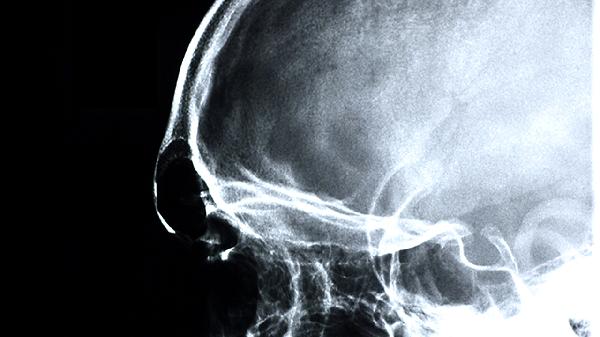

对于缺血性脑卒中恢复期出现半身不遂、口舌歪斜、言语謇涩、肢体麻木等气虚血瘀证症状的患者,心脑欣片可促进脑部血液循环,辅助神经功能恢复。使用时需配合康复训练,并定期监测血压血脂。脑出血急性期禁用该药。